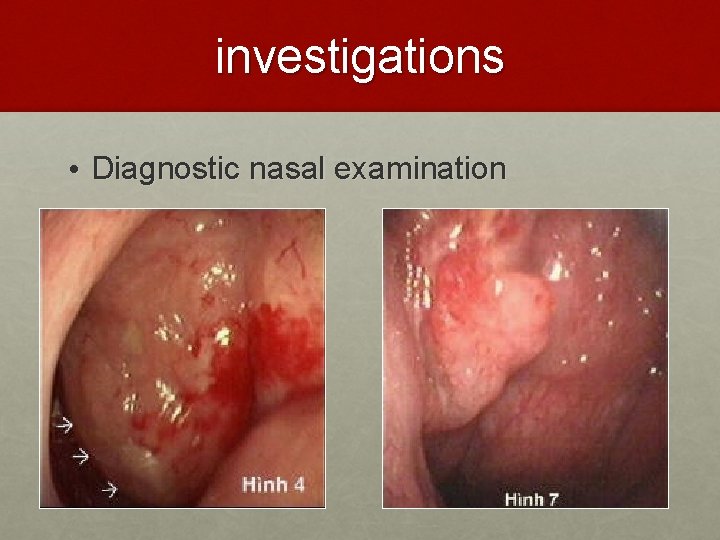

investigations • Diagnostic nasal examination